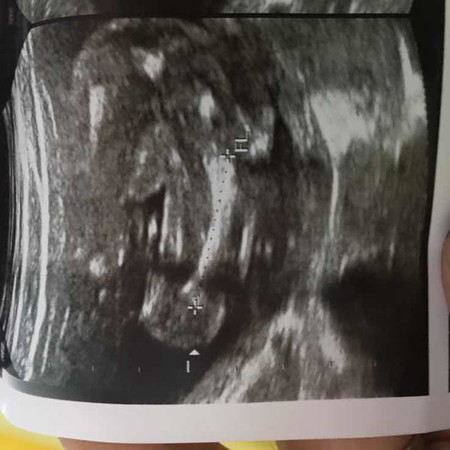

อยากรู้เพศลูก

แบบนี้ผู้ชายจิงๆๆใช่ไมค่ะ แม่อยากรู้ค่ะท้องแรกดูไม่เป็นค่ะ